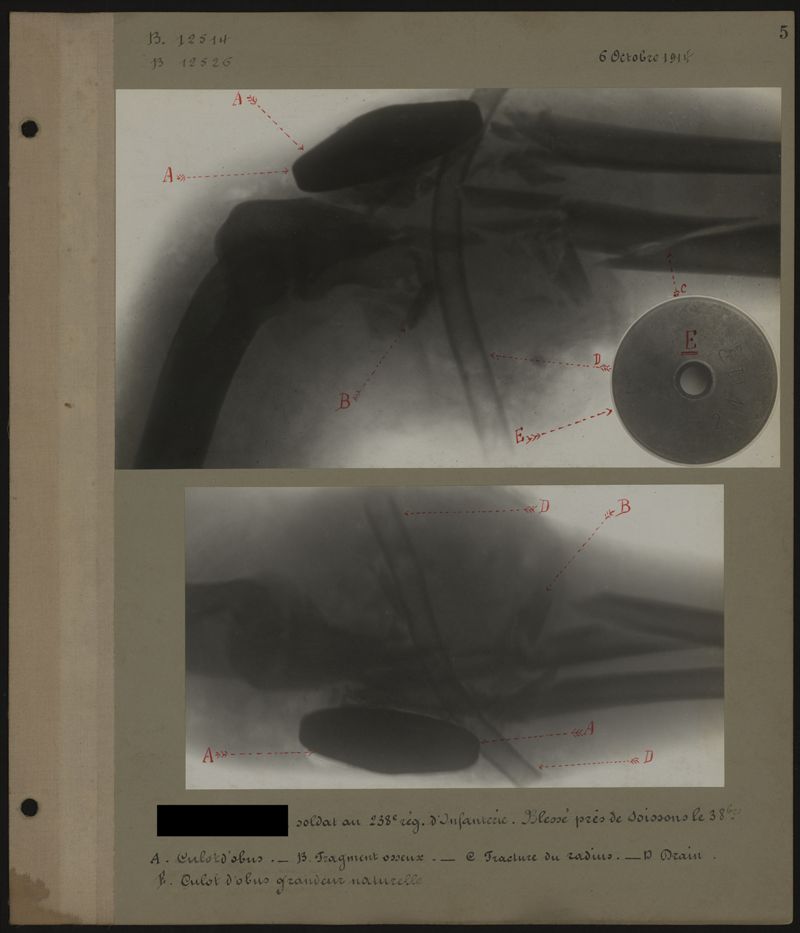

Deux albums de radiographies de la Première Guerre mondiale. Collection du laboratoire central de radiographie de la Salpêtrière. Premier album.

1914.